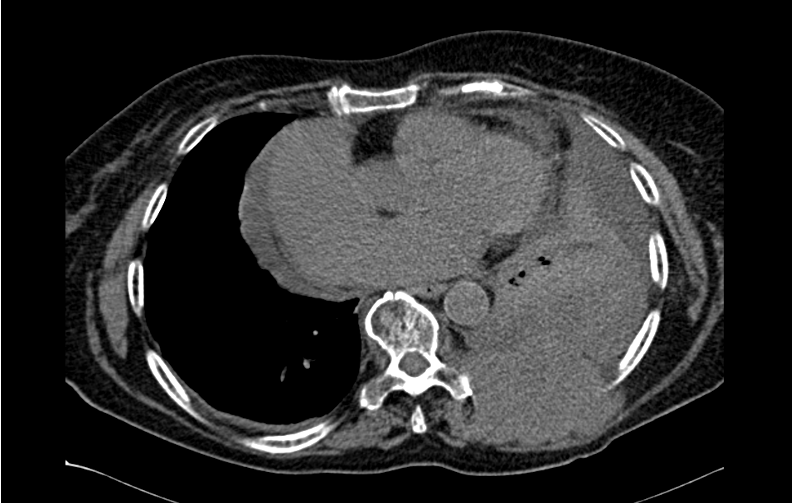

Malignant Rhabdoid Tumor of the Kidney in an 11-Month-Old Child: Case Report and Literature Review

Laura Mendes Lopes, Fabricio Grenteski, Carlos Roberto Naufel Júnior , Guilherme Andrade Coelho, Guilherme Ferrarini Furlan, Nertan Tefilli, José Anderson Feitoza , Igor Luna Peixoto